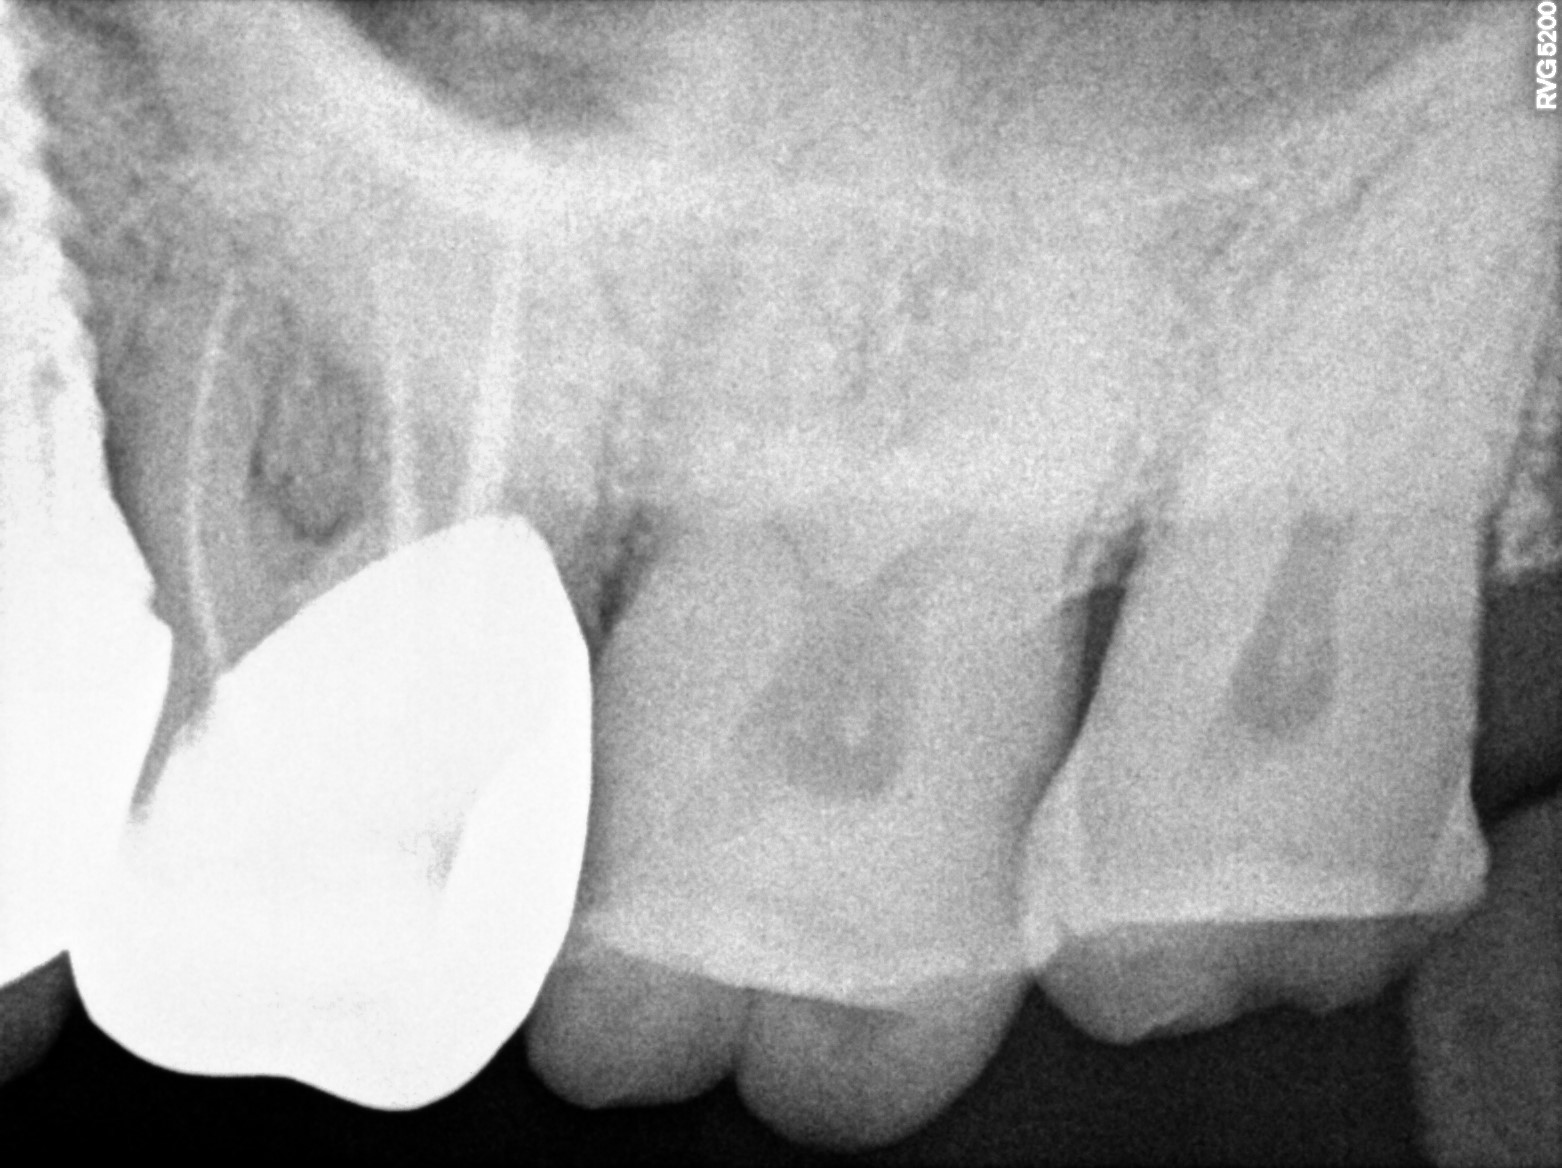

Dental Radiographs FHIR: DocumentReference · LOINC 24641-7

R53 (2).jpg

24641-7